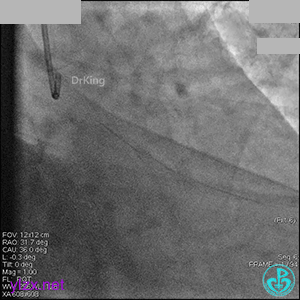

AL 1.0指引导管到位,简单短时尝试导丝不能顺利通过前降支或回旋支病变。改变策略处理右冠脉病变,计划植入2枚支架。AL指引导管到位,Sion blue导丝到达右冠脉远端。导丝通过后1.5mm及2.5mm球囊14~16atm充分扩张中段病变。